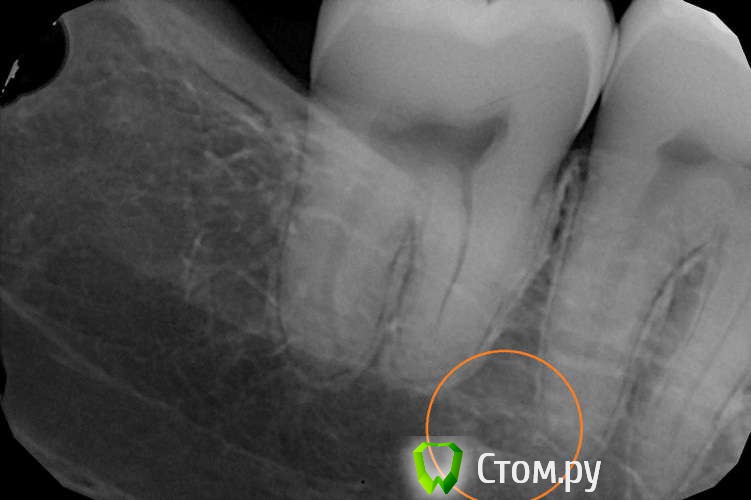

winnt Опубликовано 20 июля, 2014 Автор Поделиться Опубликовано 20 июля, 2014 red_butler, подскажите плиз еще по одному зубу, беспокоит уже больше года, два раза делали эндо, теперь вот иду в пятницу на его удаление (думаю все проблемы из-за выведенного силера) Периодически болит, перкуссия слабоболезненная (особенно со стороны неба) в щеке над ним часто как будто тяжесть или покалывания, утром чувство что есть припухлость в щеке над этим зубом. При пальпации со стороны в сторону зуба - чувство стягивания в щеке усиливается.Спасибо. Ссылка на комментарий

winnt Опубликовано 20 июля, 2014 Автор Поделиться Опубликовано 20 июля, 2014 Забыл добавить, после повторного эндо симптомы пропали на две недели, а потом усилились Ссылка на комментарий

red_butler Опубликовано 20 июля, 2014 Поделиться Опубликовано 20 июля, 2014 Снимки не информативны, выложите срезы Кт в других плоскостях Ссылка на комментарий

winnt Опубликовано 20 июля, 2014 Автор Поделиться Опубликовано 20 июля, 2014 (изменено) Вот еще пару снимков:Видео: видео_1 , видео_2 Изменено 20 июля, 2014 пользователем winnt Ссылка на комментарий